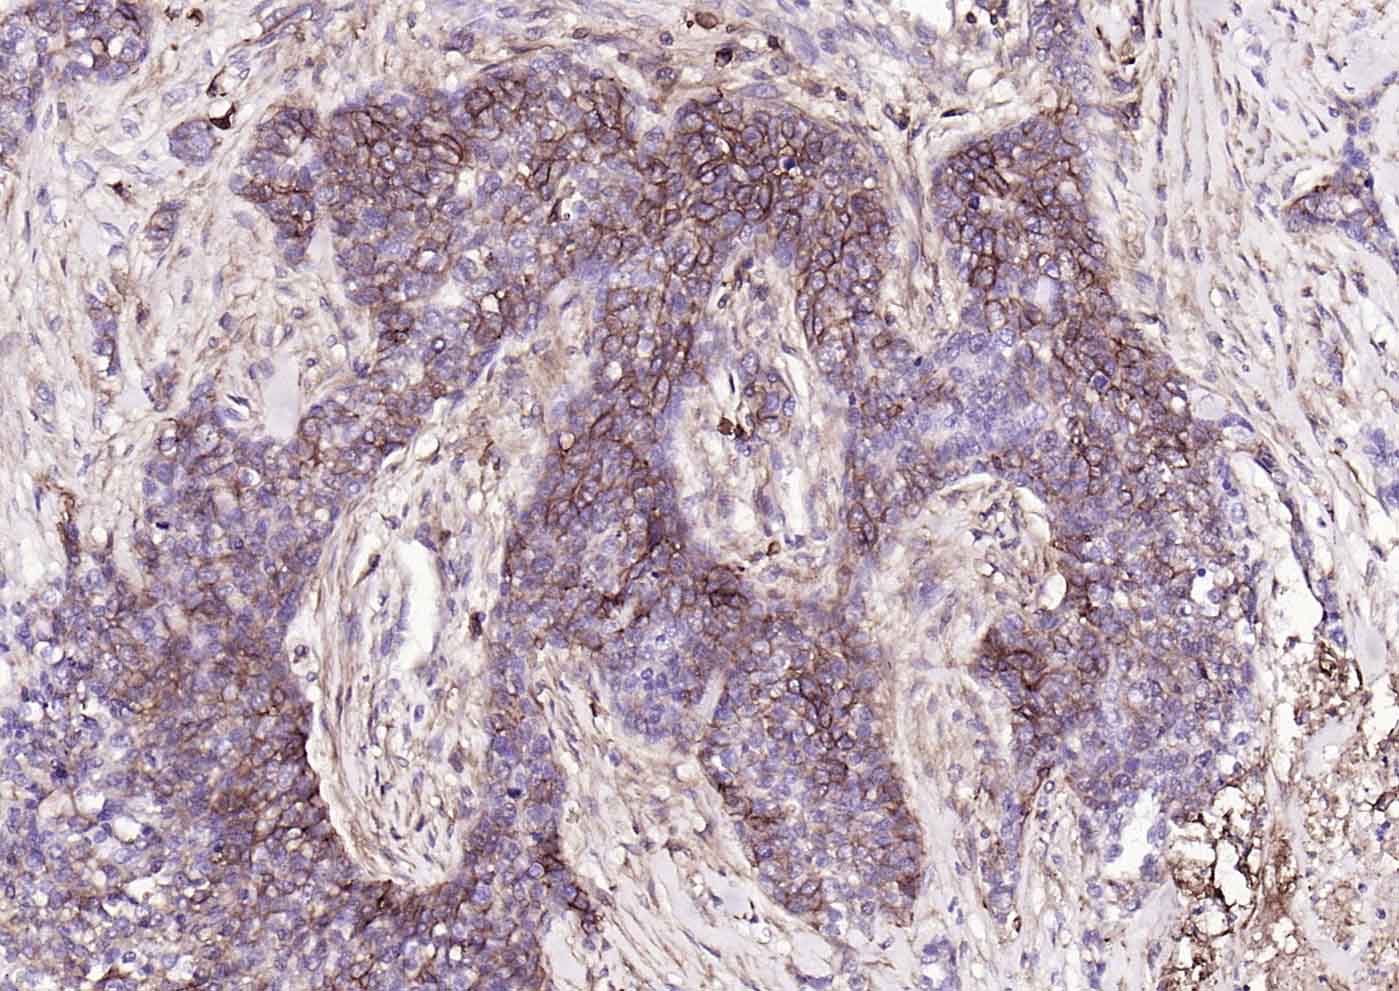

| 应用 | 已检合格种属 | 预测种属 | 推荐稀释比例 |

|---|---|---|---|

| IHC-P | Human | 1:100-500 | |

| IHC-F | Human | 1:100-500 | |

| IF | Human | 1:100-500 | |

| Flow-Cyt | Human | 1ug/Test | |

| ICC/IF | Human | 1:100-500 |